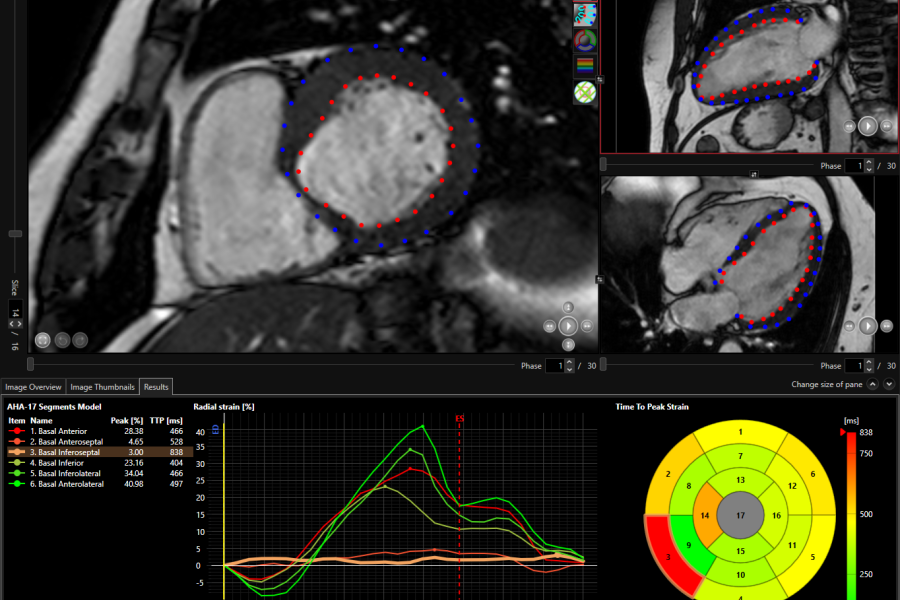

• Three strain types are determined: longitudinal, circumferential, and radial;

• Global Longitudinal Strain including Peak Strain (%) and Time to Peak Strain (ms);

• AHA 17 segment model including strain type choice;